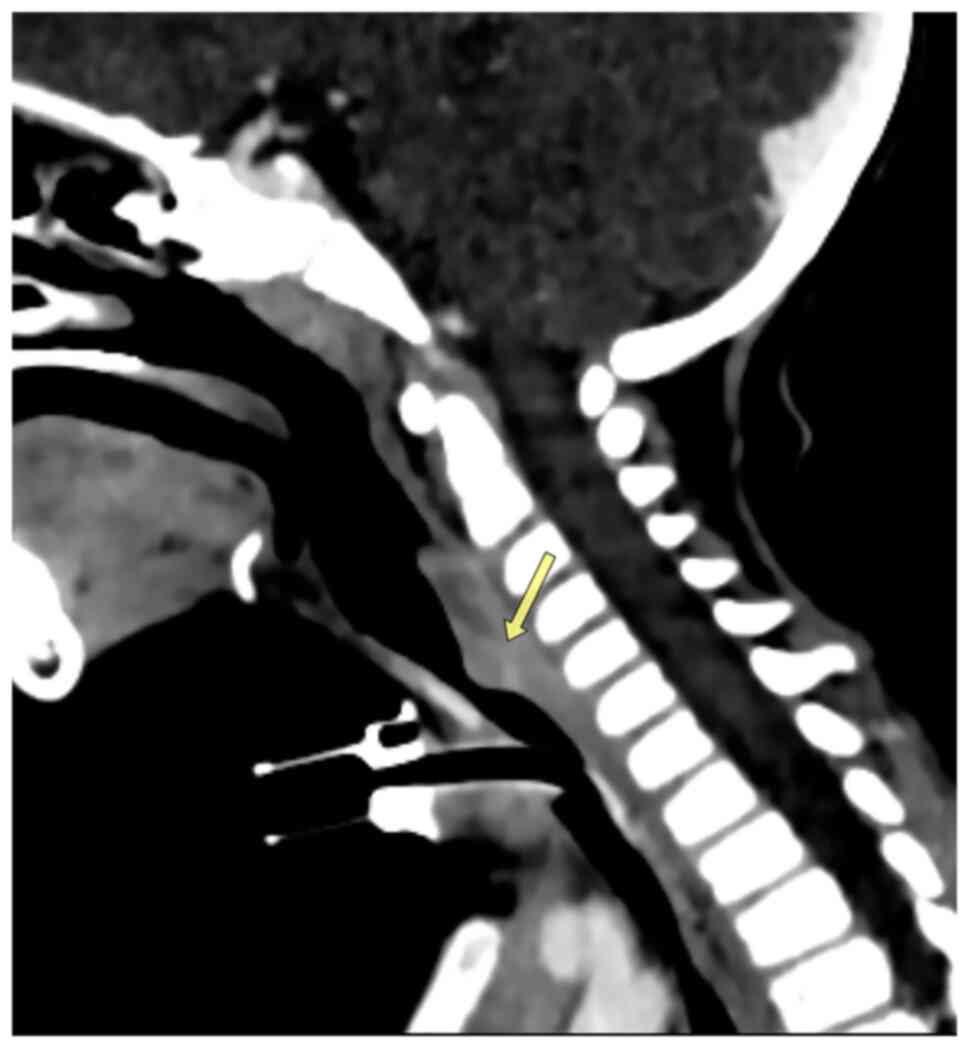

A lateral post-nasal space X-ray was performed, which illustrated tracheal stenosis (Fig. 1). A computed tomography (CT) scan was conducted and confirmed severe subglottic stenosis and a narrowing of the tracheal region just below the vocal cords (Fig. 2).

Figure 2

A sagittal contrast-enhanced post-tracheostomy neck computed tomography scan illustrating severe luminal stenosis of the cervical trachea (~70%) by enhancing a mass that protrudes from the posterior tracheal wall (arrow).